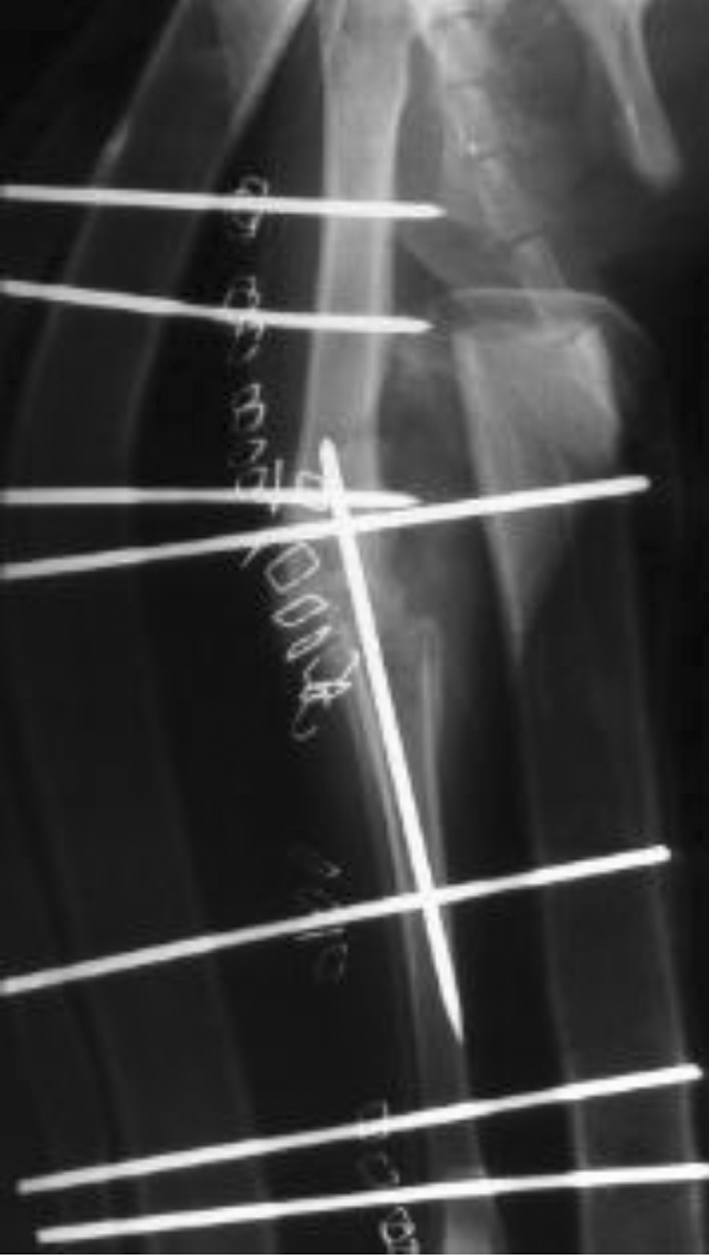

- Verplaatsen van de beenkam op het onderbeen, hierdoor wordt de knieschijf meer naar buiten getrokken waardoor hij gemakkelijker in de sleuf van de femur blijft.

-

- pijltje wijst de verplaatste beenkam aan

- Het uitdiepen van de sleuf in de femur, hierbij wordt met een speciaal freestoestel de sleuf uitgeslepen en gepolierd. De patella komt dieper in de sleuf te liggen en kan niet meer luxeren.

- In erge gevallen worden alle drie de technieken op dezelfde knie gebruikt.

- Dieren waarbij we de knieschijf niet meer op zijn plaats kunnen leggen moeten, helaas, een arthrodese ondergaan waarbij we het hele kniegewricht vastzetten waardoor de pijn weg is maar ook de bewegelijkheid van het kniegewricht

- Artrodese : de knie is vastgezet